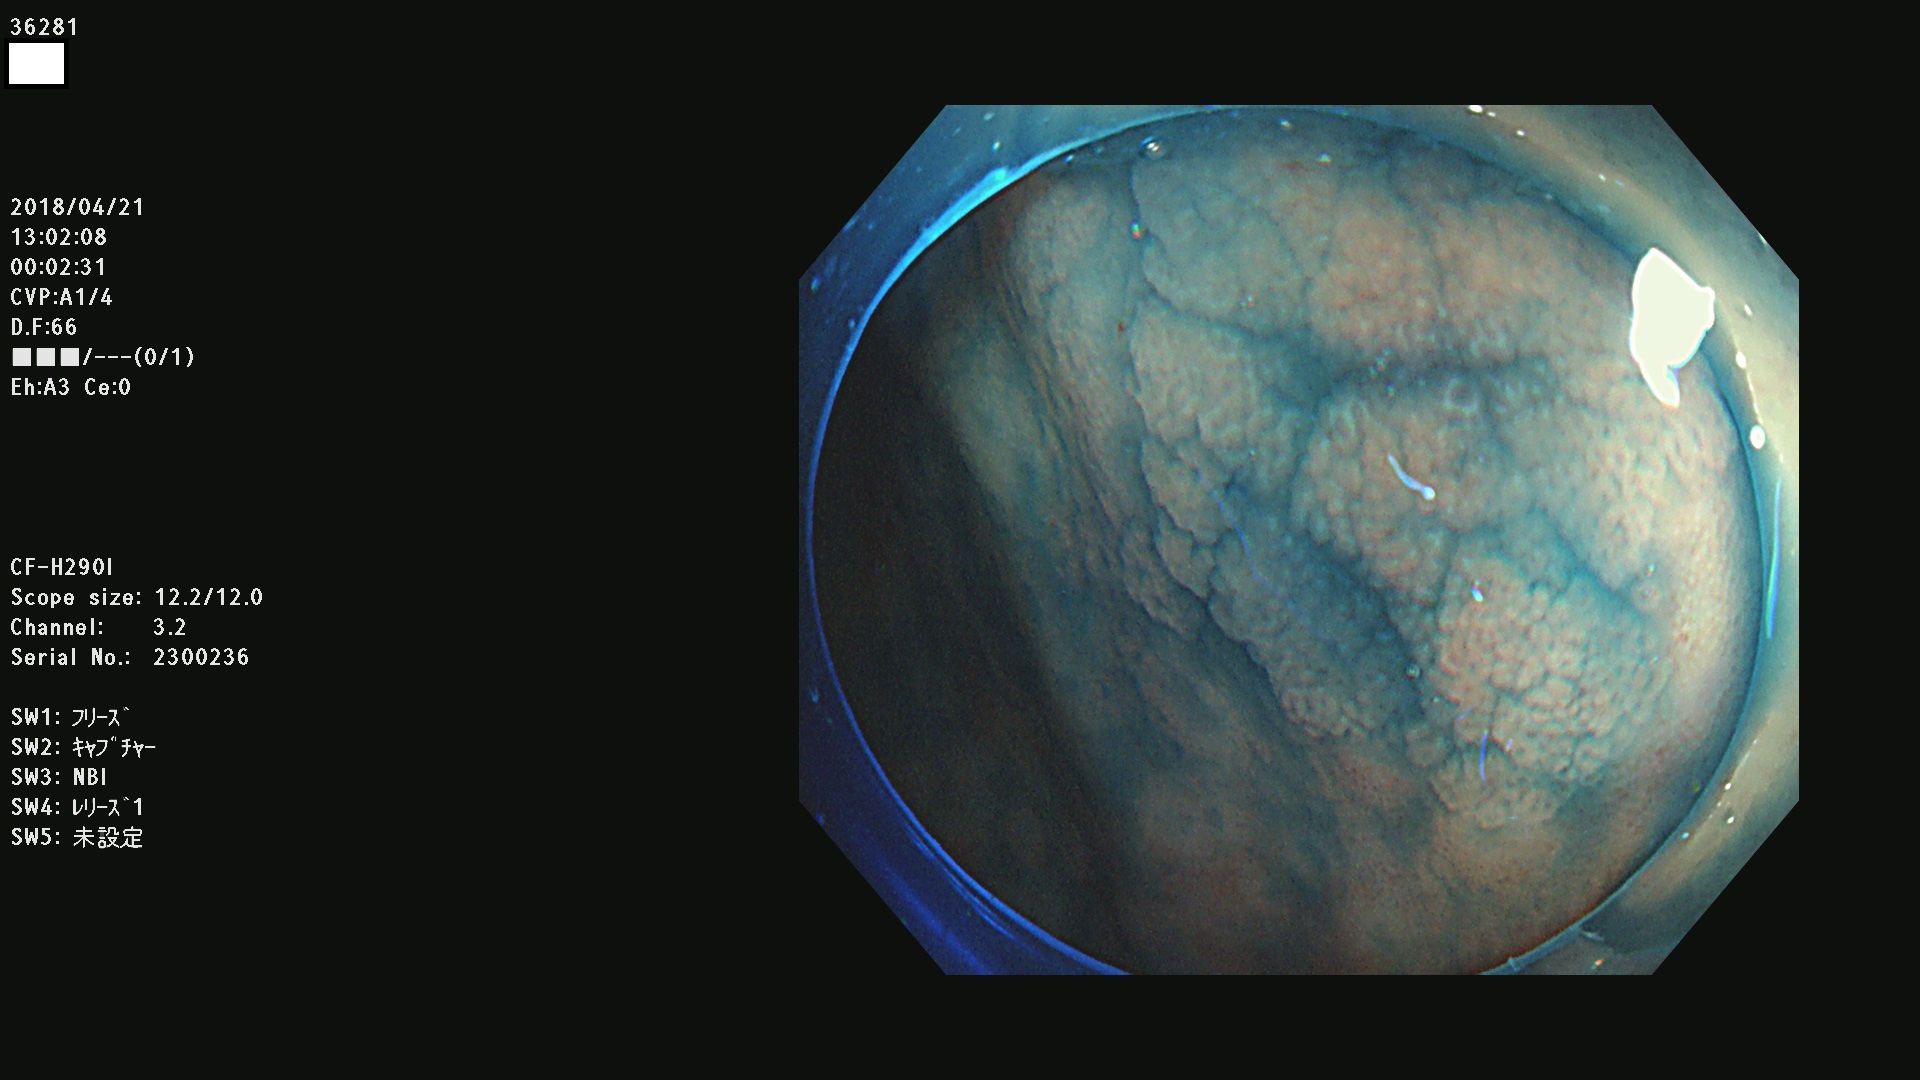

36201 36202 36203 36205 36207 36209 36210 36212 36213 36214 36215 36217 36220 36221 36222 36224 36225 36226 36227 36229 36230 36231 36232 36235 36236 36238 36240 36243 36244 36246 36247(SSAPのみ。SPS) 36248 36249 36251 36252 36253 36254 36255 36256 36257 36258 36259 36261 36262 36264 36265 36267 36269 36270 36272 36274 36275 36276 36279 36280 36281 36283 36285 36288 36289 36291 36292 36295 36296 36297 36299

発見困難で危険性の高い平坦型病変(上記100名より抽出)